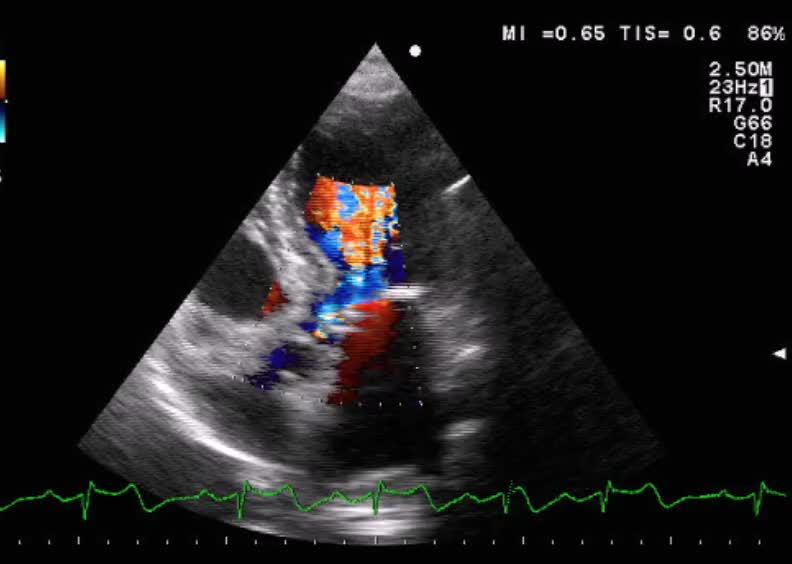

Ostruzione dinamica dell’efflusso VSx

Laura Massironi